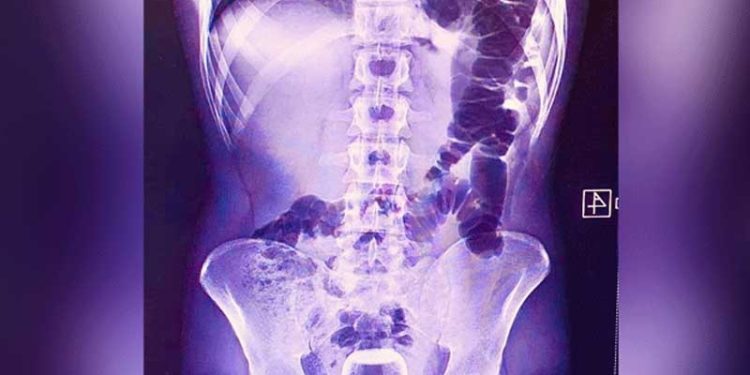

Urfa’da geçen cuma günü yaşanan olayda ismi açıklanmayan bir kişi Mehmet Akif İnan Eğitim ve Araştırma Hastanesine başvurdu. Acil serviste hastanın çekilen röntgeninde anüs bölgesinde çay bardağı görüldü. Çay bardağı, uzman doktorlar tarafından gerçekleştirilen operasyonla çıkarıldı.